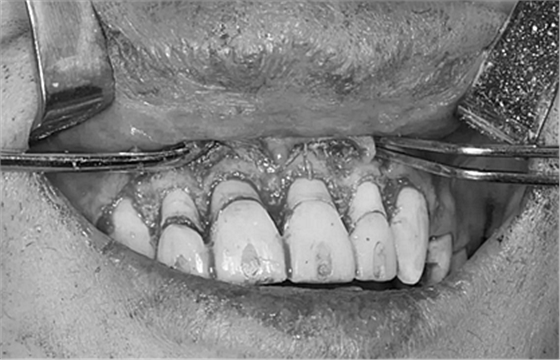

第二次治療是半個(gè)月后,這次做了根管充填后將覆蓋在我們身體上的一部分牙齦切除,讓我們埋于牙齦下的身體暴露了一部分,也就是醫(yī)生說的冠延長(zhǎng)術(shù)。這是為了讓我們變得美觀一些。

冠延長(zhǎng)術(shù)